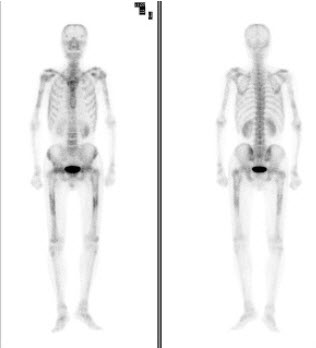

267、单项选择题

男性,48岁,血象示三系减少,双侧下肢疼痛,既往有鼻咽癌病史,行全身骨显像如图,最可能的诊断是()

A.双侧肱骨、股骨转移癌

B.四肢骨上段血液病骨损害

C.双侧肱骨、股骨肥大性骨关节病

D.恶性淋巴瘤骨浸润

E.以上都不是